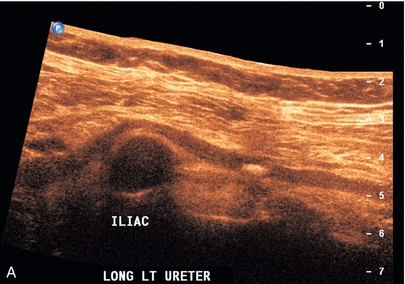

Нефролитиаз

Цветная допплерография должна быть рутинным компонентом ультразвукового исследования почек при подозрении на нефролитиаз. Сама по себе шкала серого имеет низкую чувствительность к небольшим камням в почках. Использование цветного допплера для определения мерцающего артефакта 19 может повысить уверенность в наличии камней в почках, мочеточниках или мочевом пузыре ( рис. 9-7 ). Неровная поверхность камня вызывает доплеровский сдвиг, который проявляется в виде шумного цветового и спектрального сигнала. Это помогает подтвердить, что яркий эхогенный фокус в воротах почки действительно является конкрементом, а не яркой эхогенной жировой тканью ворот почки. Этот метод следует использовать для демонстрации наличия камня, а не для измерения его размера. Это особенно полезное дополнение для оценки дистального камня мочеточника с помощью эндовагинальной техники, когда во время беременности обнаруживается расширенная собирательная система верхней почки ( рис. 9-8 ).